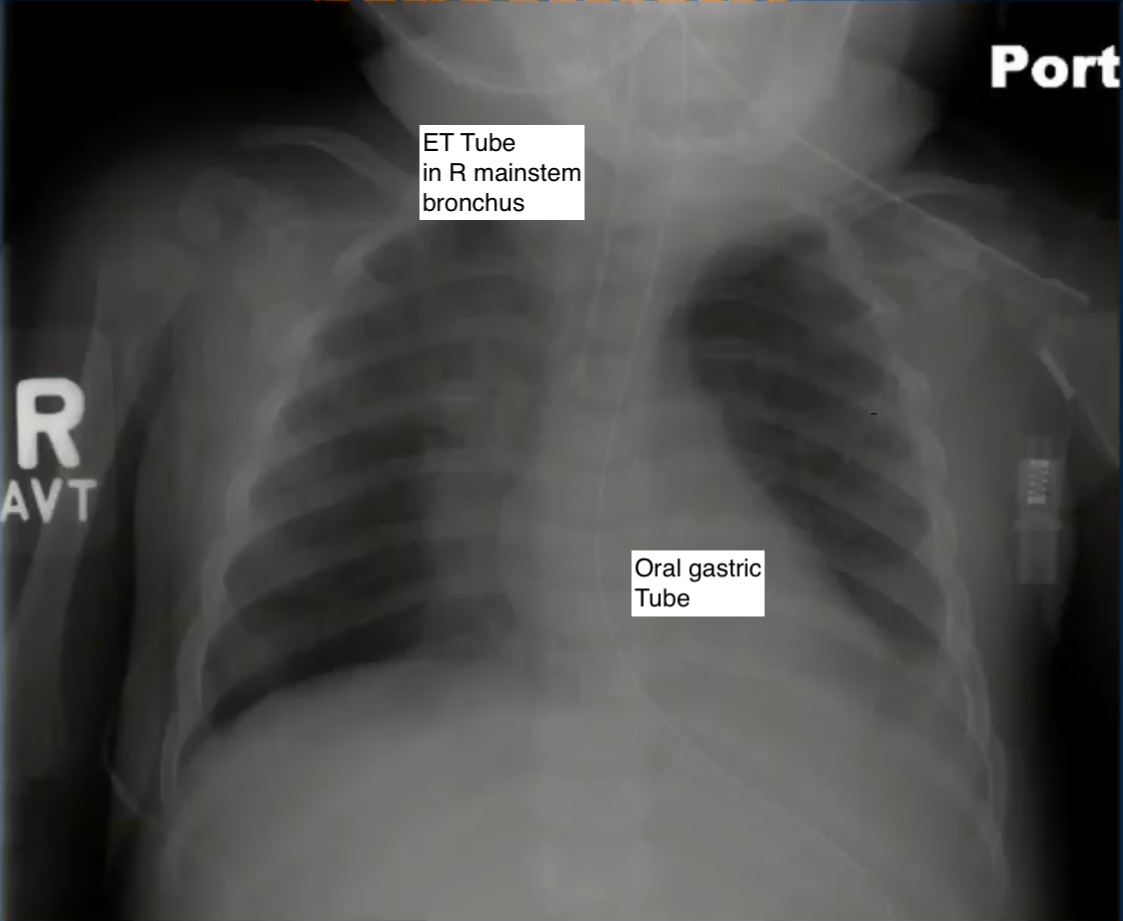

Tube placement